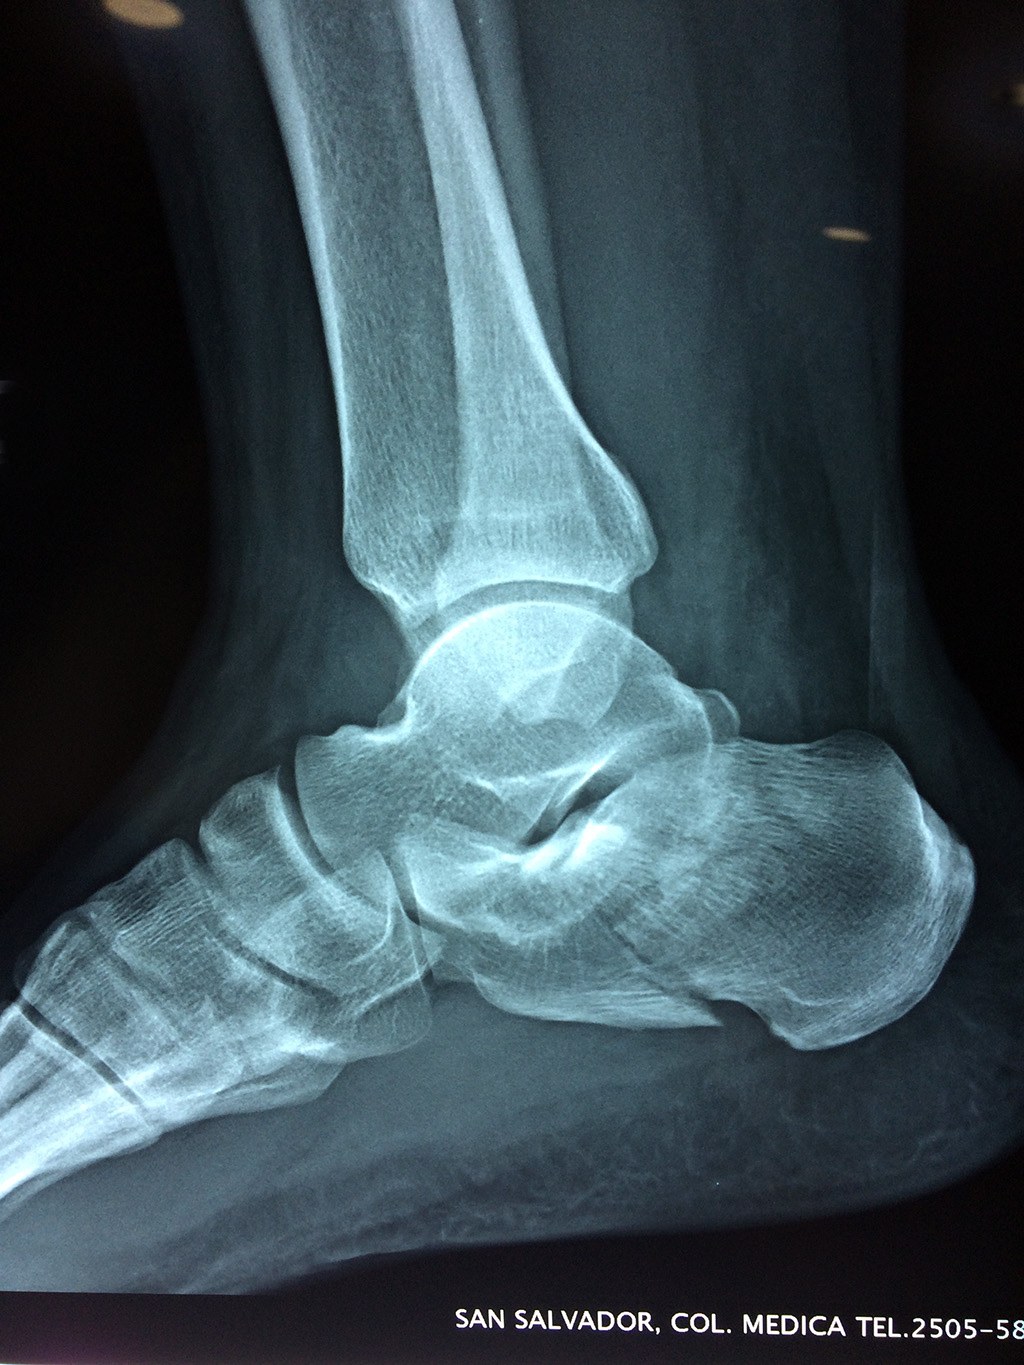

El calcáneo (del latín Os calcis) es un hueso del pie (tarso), corto, asimétrico, de forma cúbica irregular, con seis caras: superior e inferior, laterales y anterior y posterior, de las cuales dos son más o menos articulares.

Este hueso constituye el talón del pie. Se encuentra en la parte inferior de la primera fila del tarso. Se articula con el astrágalo por arriba y con el cuboides por delante. Constituye el primer punto de apoyo del pie durante la marcha, situándose en una de las zonas peor irrigadas del cuerpo y protegido plantarmente por la almohadilla plantar de tejido adiposo, con función amortiguadora.

En su cara posterior recibe la inserción del tendón más plantar, implicada en diversas enfermedades como la fascitis o el espolón calcáneo. La posición del calcáneo en relación al astrágalo (articulación subastragalina) y al suelo determinan la posición de retropié en varo, en valgo o neutra.

Los retropiés varos y sobre todo, los retropiés valgos, son responsables de distintas enfermedades del aparato locomotor y contribuyen a que aparezcan alteraciones de la marcha normal fisiológica, con consecuencias clínicas importantes (dolor, sobrecargas, aplanamiento, fatiga muscular, juanetes, etc.) tanto a nivel de pie como a nivel del miembro inferior.

De todo esto se deriva que su posicionamiento espacial es muy importante para contribuir a una marcha correcta y a la salud del resto del conjunto articular del pie.